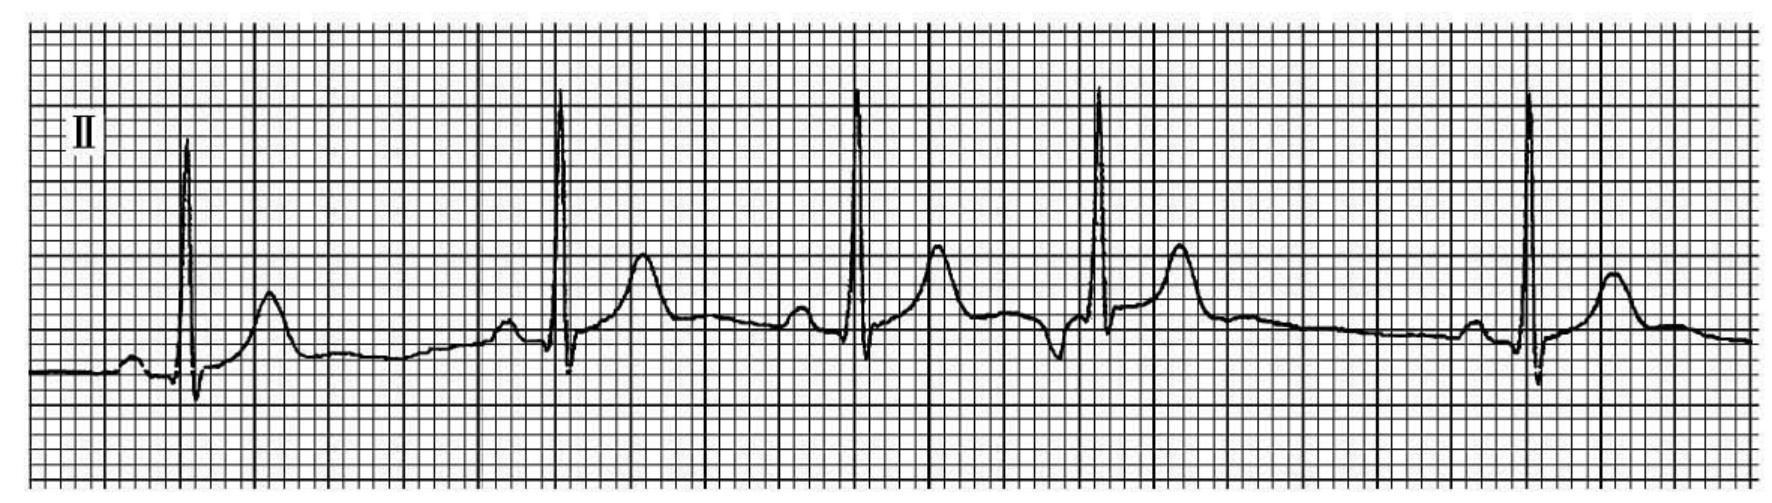

1.延迟出现的1~2次宽大畸形QRS-T波群,QRS时限≥0.12s。通常T波与QRS主波方向相反(图29-8、9)。

2.室性QRS波群前、中、后可有窦性P波,P-R间期小于0.12s,二者无传导关系;有时室性QRS波群之后可有或无逆行P波,其R-P-间期小于0.20s。

3.逸搏周期1.5~3.0s,频率20~40次/min,称为室性逸搏;若逸搏周期大于3.0s,频率小于20次/min,则为过缓性室性逸搏。

6.室性逸搏连续出现3次或3次以上,称为室性逸搏性心律。室性起搏点自律性强度不稳定,故心室节律多不齐(图29-10)。

图29-8 窦房传导阻滞伴发室性逸搏、完全性右束支传导阻滞